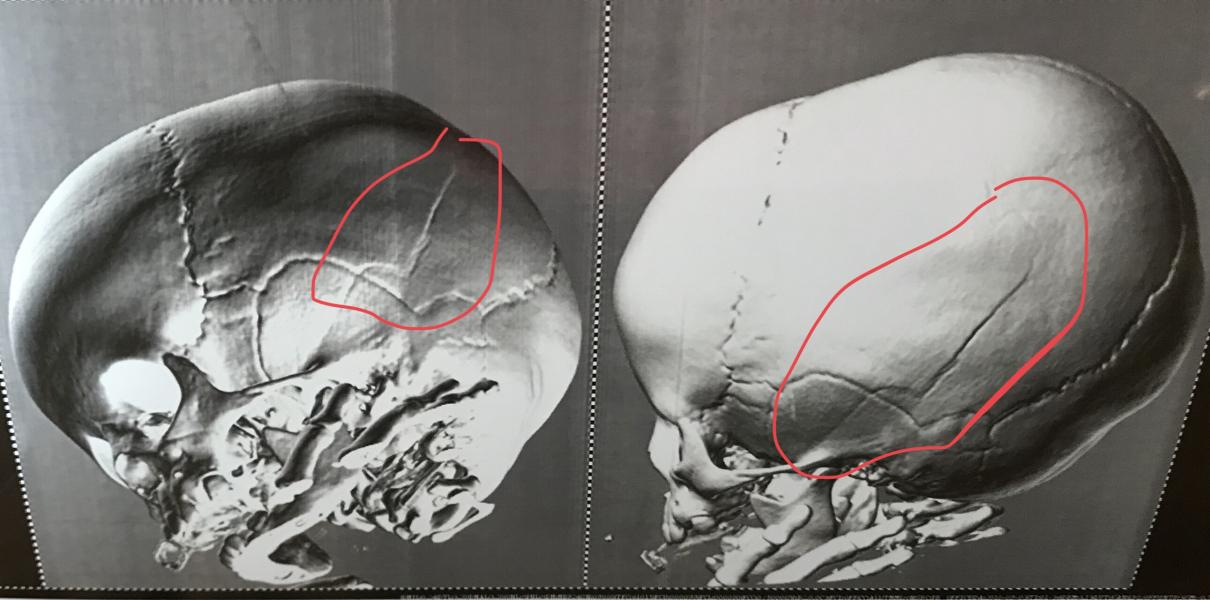

В результате сотрясение, ушиб головного мозга, трещина через 2 кости и гематома огромная!!! Благо, что наружу вытекла, а не в мозг...